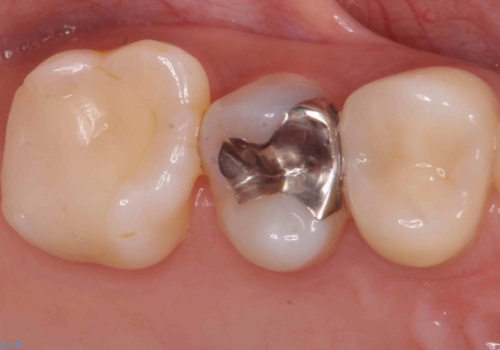

ブリッジでの修復は、抜歯後に歯がなくて噛みにくい期間が一切ありません。

歯茎の状態も良く、適合の良いブリッジを装着することができました。